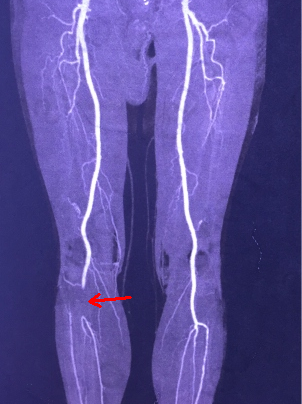

在绝望之际,患者家属经多方打听,慕名来到河南省血管外科主委单位、河南省医学重点培育学科——郑州大学五附院血管外科就诊。医院副院长、血管外科专家王兵教授接诊后,仔细研究了患者的病历资料及影像学资料(图1),考虑患者为“下肢动脉硬化闭塞症合并右下肢动脉血栓形成”。鉴于患者在外院已尝试置管溶栓治疗,但效果差,只有进行“杂交手术”才有可能挽救患者肢体。所谓“杂交手术”,即先经传统手术切开取栓,再通过球囊或支架置入的腔内方式解决原发的狭窄或闭塞性病变。

图1 术前CTA,右侧腘动脉闭塞